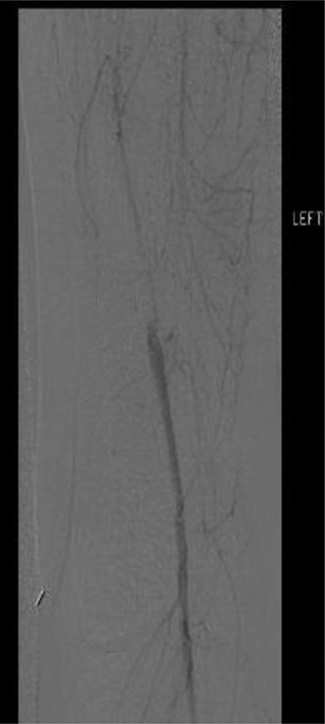

Workup began with noninvasive studies of the left lower extremity displaying aortoiliac occlusive disease and infrainguinal disease. Aortogram demonstrated a severely calcified aorta, patent left common iliac and proximal hypogastric arteries, with occlusion of the left external iliac, left common femoral and left superficial femoral arteries (Fig. 1). The right iliac system was patent apart from an occluded right hypogastric artery. A selective left lower extremity angiogram demonstrated reconstitution of the mid-to-distal profunda femoris artery (Fig. 2) to the proximal above-knee popliteal artery at the adductor hiatus (Fig. 3). Extensive collateralization was appreciated in the pelvis and lower extremity, between the residual left hypogastric artery and profunda femoris artery. Endovascular revascularization attempts were unsuccessful.

Selective left lower extremity angiogram demonstrating reconstitution of the above-knee popliteal artery at the adductor canal